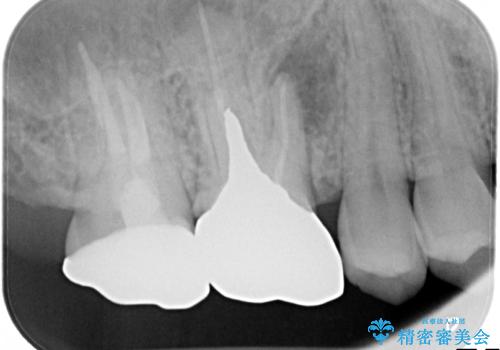

根っこの感染 再治療をしてかぶせ物を製作する

- 古いかぶせ物・土台・根管充填材をすべて除去し、内部を徹底的に洗浄する

→改めて土台を築造し、かぶせ物を新製する

根管治療を丁寧に仕上げることで、長く安心してかぶせ物を使っていただくことができます。